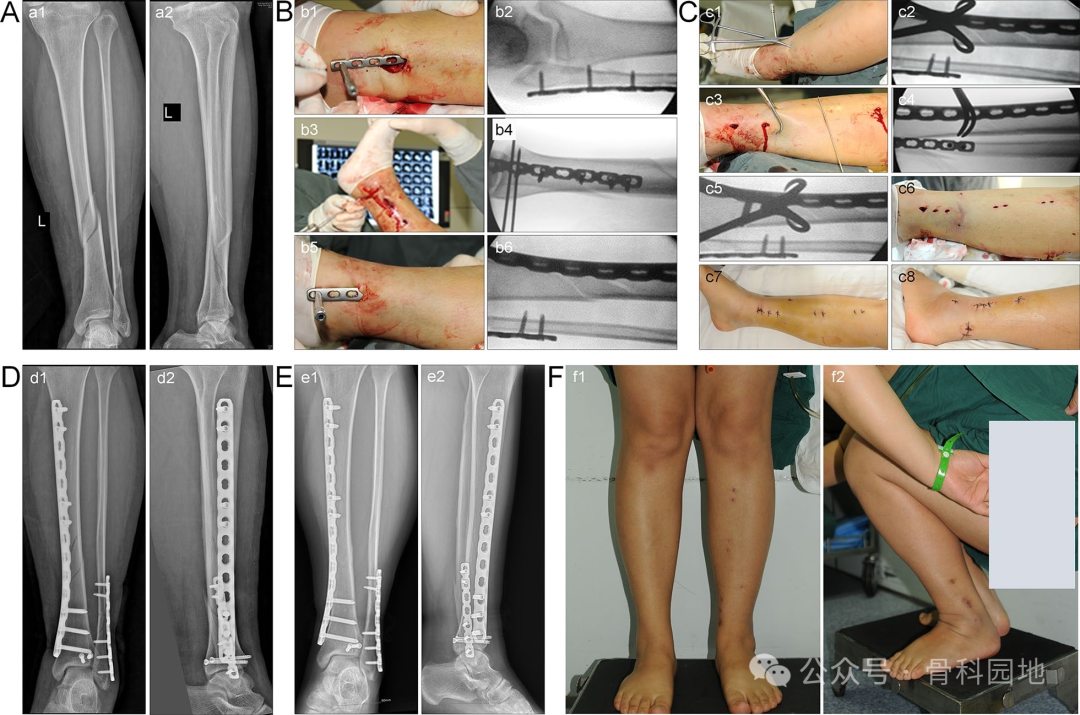

使用MIPO技术。准备一个内侧皮下骨外隧道,然后将钢板植入隧道中。调整位置使钢板紧贴骨表面后,用克氏针或钻头暂时固定靠近切口部位的钢板末端(下图A,B)。使用c臂透视从正位和侧位角度评估钢板的位置以及骨折的位移和角度畸形。通过手动牵引或牵开器复位纠正骨折的缩短和旋转移位。选择合适的点复位钳来维持位置(如下图E、F)。

下图中的患者患有胫骨、腓骨和后踝骨折(图A)。在固定腓骨和后踝后,通过钢板辅助的经皮夹持技术有效地纠正了胫骨外侧移位(图B,C)。治疗后,患者获得了良好的骨折复位、骨愈合和功能恢复情况(图D-F)。